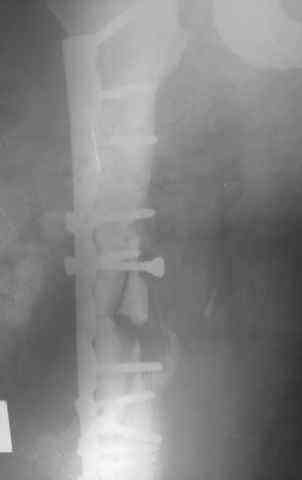

Несрошийся открытый фрагментарный, оскольчатый, перелом в/с/3 правого бедра с размозжением мягких тканей. Состояние после ПХО,МОС,ВО ЧКФ стержневым АВФ. 10.10.09.Заживление раны per prima. Операция:16.12.09,открытый накостный МОС,аутокостная пластика(из крыла подвздошной кости)правого бедра. После п/о периоде заживление раны вторичным натяжением (на 5-е сутки распущены швы, после очищения раны наложины вторичные швы) На этапных RO-гр:остеолизис костного трансплантата и дистального фрагмента перелома бедра. Вопрос:дальнейшая тактика лечения-БИОС аутокостная пластика (трансплантат на сосудистой ножке М/Б кости). Билокальный остеосинтез по Илизарову с остеотомией подвертельной и надмыщелковой области бедра. Мозможен ли аутотрансплантат без сосудистой ножки? Чем улучшить васкуляризацию? Декортикация? Тактика выжидания остеолизиса, а затем оперативное лечение.